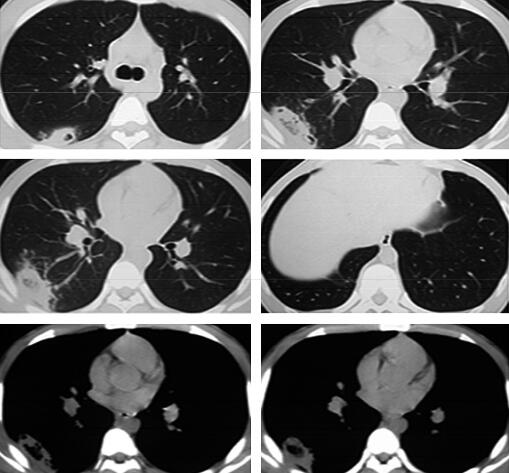

4天后热退,复查血常规白细胞计数及中性粒细胞百分比均恢复正常,治疗似乎有效,但此时患者出现咳铁锈色痰,偶有新鲜血痰,2013年2月27日复查胸部CT示右下叶后基底段原斑片影吸收,但背段有新发小片状阴影,带有小空洞,外基底段病灶也出现多发小空洞(图2),此时本该引起警觉却被“体温下来是硬道理”给冲昏了头脑,关键症状咯血也想当然的用肺炎解释了,治疗上联合左氧氟沙星氯化钠静脉滴注以加强抗感染治疗,2013年3月5日复查胸部CT(图3)可见右肺下叶背段病灶较前缩小,而外基底段斑片状渗出影较前明显吸收,更让医生坚定了肺炎的诊断。但此时的病人仍有气短(仅活动时)和轻度胸痛,咯血有加重倾向,最多一次量约5ml,呈鲜红色,这时医生感到困惑了。

图2

图3